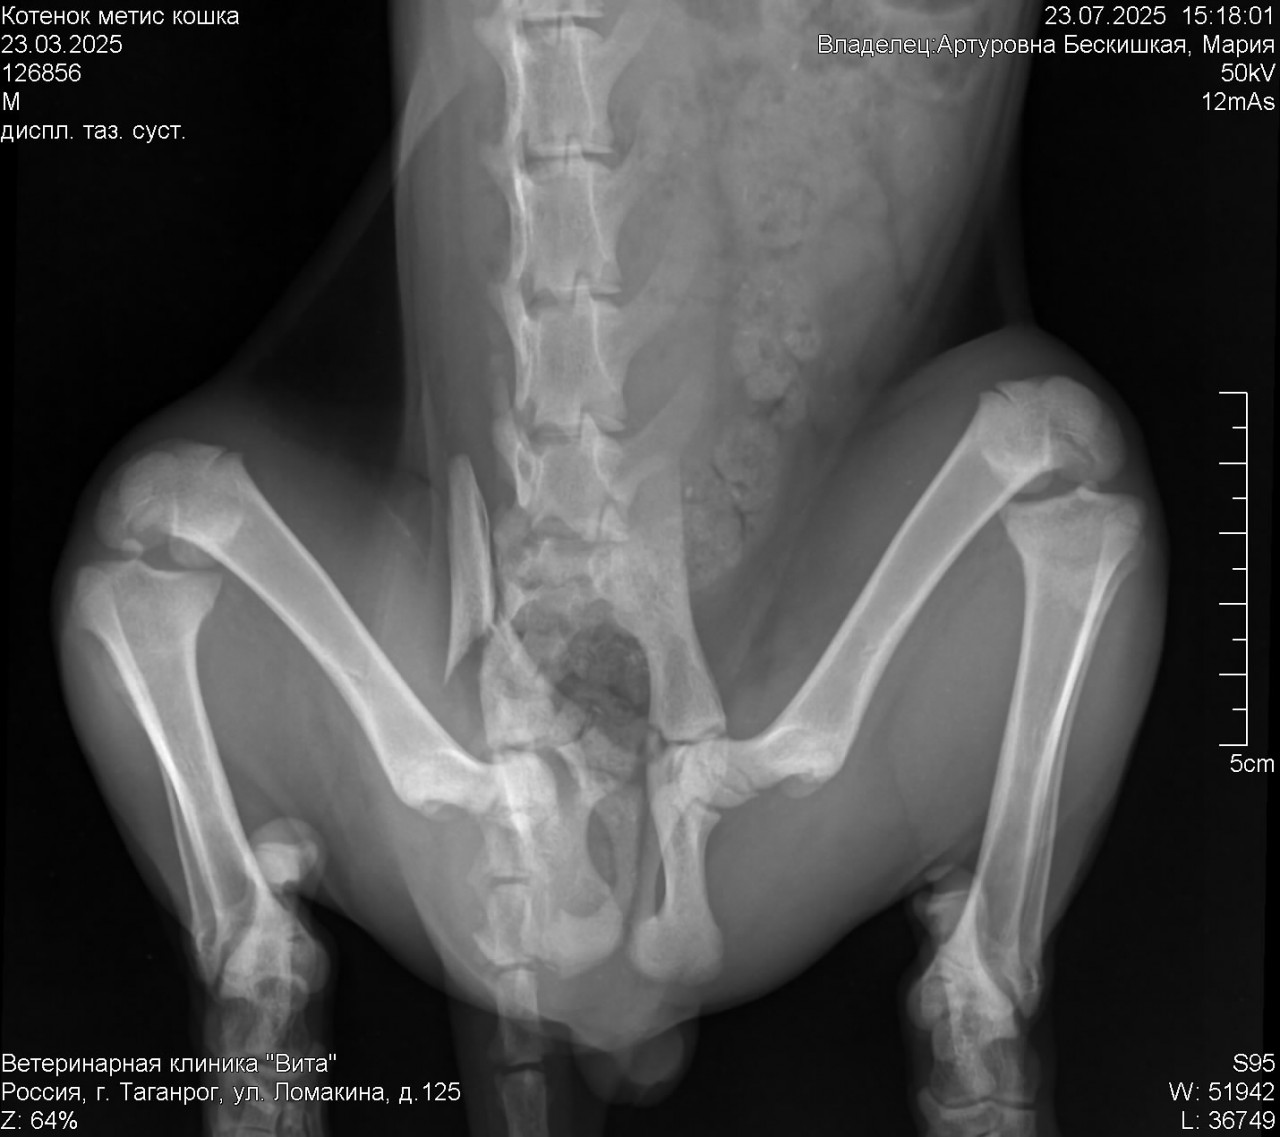

добрый день подобрали котенка упал с 12 этажа ,после объявились хозяева котенок оказался им не нужен . Вчера обнаружили перелом таза . Котенок уже кушает ,после обезбола стал сам мочится ,но по большому еще не ходил .

Действительно ли если котенок сам будет ходит в туалет ему не нужна операция? Не вызовет ли это проблем в будущем ? Снимок прикрепила

Здравствуйте. По рентгену у котёнка действительно отмечается перелом таза, но без выраженного смещения, которое угрожало бы жизненно важным функциям. Если он уже самостоятельно мочится это хороший признак. Дальнейшая тактика зависит от способности к дефекации и если в течение 3-4 дней котёнок начнёт ходить по большому и не будет признаков непроходимости, операция может и не понадобиться. Важно контролировать общее состояние, аппетит и живот (чтобы не появилось вздутие или болезненность).

Здравствуйте. Тактика ожидания в течение нескольких дней оправдана, особенно при стабильном состоянии и отсутствии сильного смещения костей. Основная угроза при переломах таза у котят  это нарушение работы кишечника и мочевого пузыря из-за сдавления или повреждения нервов. Если котёнок начнёт самостоятельно опорожнять кишечник и мочевой пузырь, то вероятнее всего операция не потребуется. Но в дальнейшем важно будет следить за походкой, положением таза и возможно сделать контрольный снимок. Реабилитация это покой, мягкая подстилка и при необходимости слабительные средства по назначению врача.